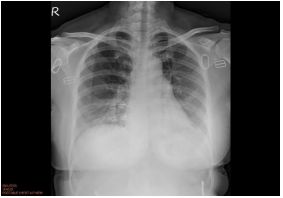

3. This 72-year-old diabetic man was taken to ER for productive cough for 10 days, and rapid progressive dyspnea for 2 days. He also had fever and chill for a week.